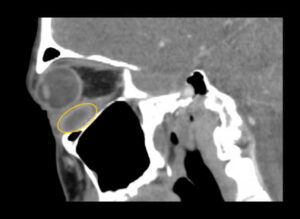

Inferior Rectus Abscess CT Sagital Annotated. JETem 2025